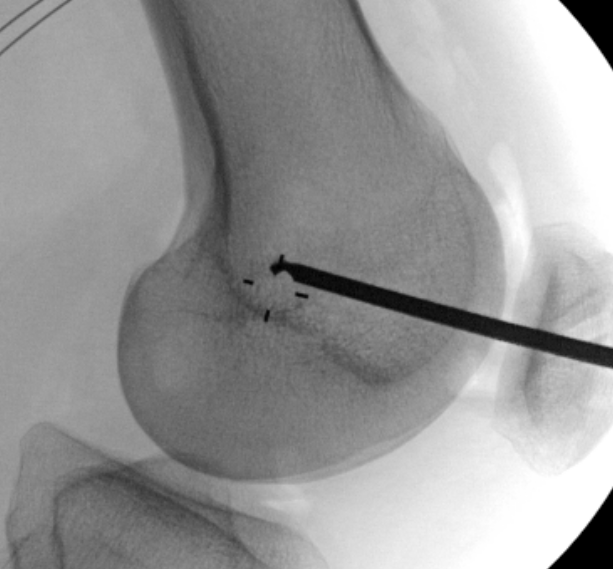

Femoral attachment

- 4 mm proximal and posterior to medial epicondyle

- image intensifier: intersection of the posterior femoral condyle with Blumensaat's line

- 40o anterior to avoid notch

SchottleMCLMCL recon